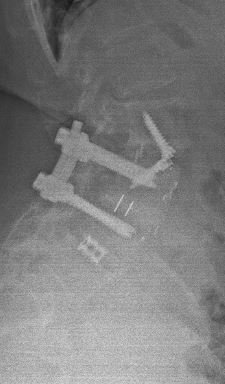

Another example is a young lady who had severe low back pain. Traditionally, fusion surgery through very large incisions would be required. With the new “percutaneous” technique of placement of pedicle screws, we were able to remove her disc through her abdomen and place screws through two small incisions in her back. She is now more than 80% improved.*